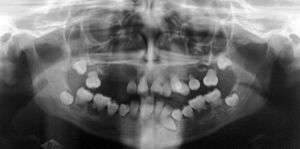

| Preoperative panoramic radiographs showing features of dentin dysplasia type I | |

Dentin dysplasia is a genetic disorder of teeth, commonly exhibiting an autosomal dominant inheritance. It is characterized by presence of normal enamel but atypical dentin with abnormal pulpal morphology. There are two types. Type I is the radicular type, and type II is the coronal type. In the radicular type, the roots of teeth are shorter than normal and the pulp chamber may be nearly gone. The pulp chamber is sometimes described as having a "crescent shaped" appearance. In the coronal type, the pulps are enlarged and are described as having a "thistle tube" appearance, in permanent dentition. In the deciduous dentition, coronal dentin dysplasia bears a resemblance to Dentinogenesis Imperfecta type II.

Type 1: Roots are short, blunt and conical. In deciduous teeth, pulp chambers and root canals are completely obliterated while in permanent they may be crescent shaped.

Type 2: The pulp chamber of the deciduous teeth become completely obliterated. The permanent teeth displays large pulp chamber in the coronal portion of the tooth - referred to as thistle tube appearance. Pulp stones may be found.